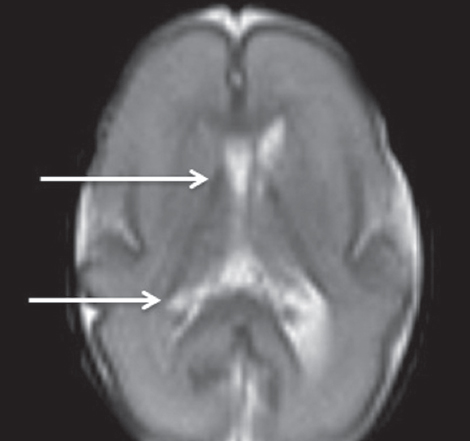

In MRI studies on premature infants at PCAs of 27–32 weeks, the germinal matrix was visualized in eight premature infants as DWI–MRI signals along the side walls of the brain lateral ventricles, as well as along the anterior horns above the caudate nuclei on both sides (Fig. 4). The germinal matrix was reliably detected in T2-weighted images from seven neonates (Fig. 5) and in T1-weighted images from two neonates (Fig. 6). The germinal matrix could not be visualized using FLAIR sequences.

Fig. 5. MRI of preterm newborn (PCA 28 weeks), Т2-WI, axial plane. Arrows mark the areas of the germinal matrix located along the external walls of the lateral ventricles (hypointense MR signal)

Рис. 5. МРТ головного мозга недоношенного ребенка (ПКВ 28 недель). Т2 ВИ, аксиальная проекция, стрелками выделены участки

In the present study, the germinal matrix could be visualized using the T1-pulse sequence in only two infants at PCAs up to 32 weeks, as a hyperintensive signal from the lower wall of the anterior lateral ventricles. Using the T2-pulse sequence, the germinal matrix was detected in seven out of nine infants at PCAs of 27–32 weeks, as a hypointensive MRI signal from the anterior sections and outer walls of the lateral ventricles. S. Counsell recommends using a T2-pulse sequence to measure cerebral maturity in premature infants [4]. S. Counsell reported a decrease in the intensity of the T2 signal from the lateral walls and anterior sections of the lateral ventricles in premature infants at PCAs of up to 32 weeks. As suggested by S.J. Counsell, the preservation of the hypointense T2 signal from these structures in premature infants with PCAs above 32 weeks may indicate a glial migration disorder [5].